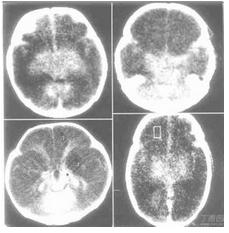

腦軟化3.恢復期 病變區往往呈現凹陷狀,較大者常為囊腫樣,囊壁可能光滑,含清亮或混濁液體,亦可能為縱橫、粗細不一的纖維囊束所橫跨形成多房狀。小者則為腔隙狀。更小者可能為較硬的瘢痕組織。

動脈粥樣硬化的病人,往往出現短暫性腦缺血發作,表現為一過性單肢癱或偏癱、肢體感覺障礙或失語等,24h內完全恢復。過去臨床醫生認為系腦血管痙攣所致,但硬化的動脈不易發生痙攣,故這種解釋已不為人們接受。根據細緻的臨床觀察,加之CT的問世以及屍檢工作的不斷探索,現在認為,這種短暫的發作,一部分由於細小栓子暫時阻塞了某一小動脈,引起功能障礙,但尚未引起組織的壞死,栓子即已脫落。正如作者曾遇一患者,左眼突然失明,檢查時發現左眼底小動脈內的玻璃樣栓子,數小時後,患者恢復了視力,眼底完全正常。另一部分,可能由於小的軟化灶形成,但離重要結構如內囊或上升性感覺纖維較遠,壓迫這些纖維所造成的輕微水腫幾小時即消失,故功能完全恢復,但軟化灶仍然存在。近來CT的套用對解釋該現象有很大幫助。如一患者病史中出現一次偏癱,但CT可能發現有3處軟化灶,說明其餘兩處並未造成症狀。有時患者從未有過卒中發作,而CT可發現2或3個軟化灶。屍檢工作者實際早注意到某些患者因一次卒中而亡,但腦內可發現另外兩個陳舊性軟化灶。說明這些靜區的病灶,若接近重要的結構,可能因水腫波及而使患者出現短暫的發作,證明許多所謂短暫性腦缺血發作並非沒有病理基礎。另一種所謂可逆性缺血性神經系統功能缺損,系神經系統功能障礙如單癱、感覺障礙、失語等,在3周內完全恢復。其症狀都是由於接近重要結構的軟化而引起。作者遇到一例患者,突然出現左側偏癱,3周完全恢復,但CT發現右側殼核有一軟化灶,這進一步說明所謂短暫的可逆性的病例,實際都是由軟化灶引起,有其病理基礎。只要臨床醫生理解發病機制,這些術語還可以保留,並有益於病人心理上的安慰。1993年Fries等報告了患者內囊後肢軟化後尚能完全恢復。他用磁共振檢查發現,內囊後肢確有軟化。這又有力說明大腦有著完備的代償功能。